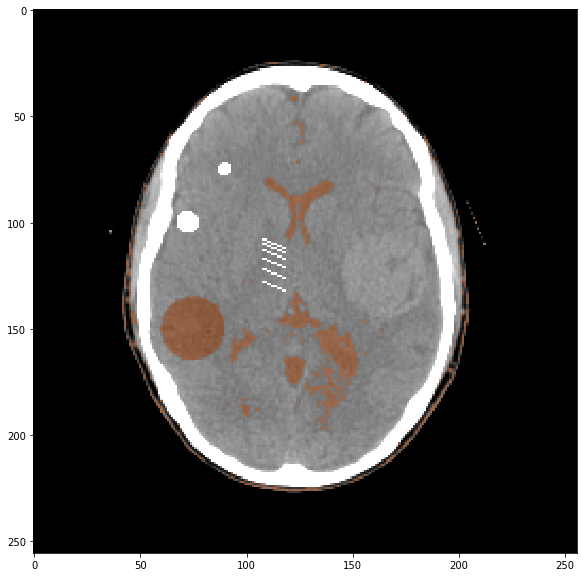

Chargez l’image ci-dessous, et regardez son sinogramme :

img = np.fromfile('CTscan.raw',dtype='float32').reshape((256,256))*scale

plt.imshow(img,**ctDisplay)

Reconstruisez l’image à partir de ce sinogramme :

La question du diffusé en particulier – et des artefacts en général – est loin d’être anodine ; non seulement la qualité image s’en trouve dégradée, mais pire encore, les applications utilisées en aval (segmentation, recalage, quantification) peuvent voir leurs performances baisser à cause d’une image de mauvaise qualité.

- Regardez l’histogramme de l’image CT “propre” ; jouez avec des seuils min et max pour isoler l’hypodensité circulaire dans la tête du patient : y arrivez-vous ? Avez-vous des idées pour nettoyer votre segmentation des pixels segmentés n’appartenant pas à l’hypodensité ?